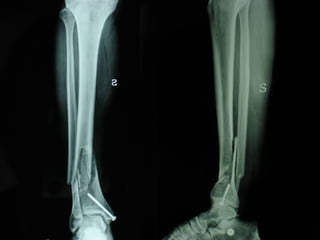

Dal Gennaio 2000 al Febbraio 2006 abbiamo trattato 167 fratture chiuse  con placca percutanea  in 164 pazienti :  27 lesioni diafisarie di gamba, 12 piloni tibiali ,  11 fratture prossimali di tibia, 36 fratture sovracondiloidee di femore, 17 fratture diafisarie di femore, 43 fratture metaepifisarie prossimali di omero, 21 diafisarie d’omero.  156 guarigioni 8 fallimenti

I buoni risultati ottenuti dipendono da 5 punti fondamentali:   una accurata riduzione percutanea della frattura  precise vie di accesso  l’utilizzo della placca che consenta il più lungo braccio di leva possibile il pretensionamento della placca  una sintesi con un ridotto numero di viti

Accurata riduzione percutanea della frattura

Precise vie di accesso

Placche lunghe e pretensionate

Placche lunghe e pretensionate Sintesi con un ridotto numero di viti